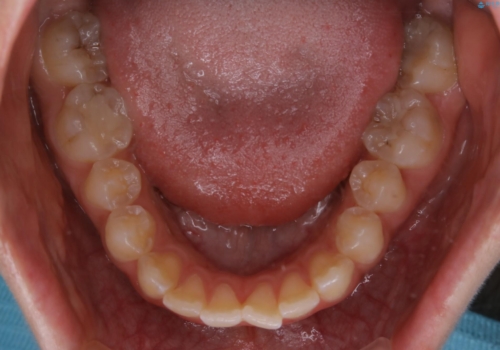

日常的に舌を突出する癖があったため、後戻り防止のために舌および口唇の筋機能訓練も合わせて行いました。

舌癖がある方は、歯を内側から押し出す力が日常的に働くため、矯正治療後も歯と歯の隙間が開いてしまうなどの後戻りのリスクが高いことが知られています。舌の正しいポジショニングやお口周りの筋肉のトレーニングを行うことで後戻りのリスクを減らすことが可能です。